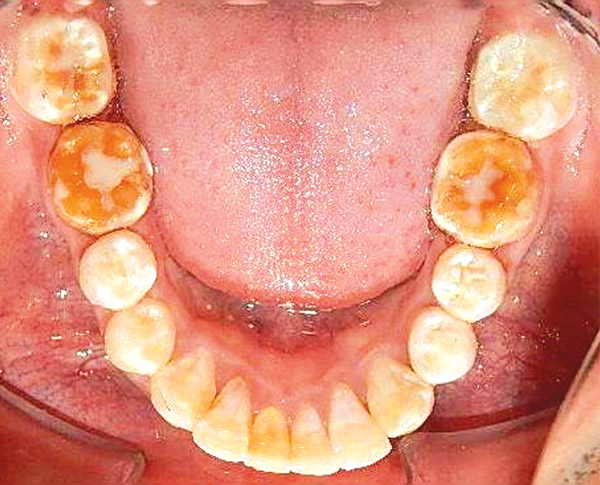

Figura 7. Inferior.

En las fotografías intraorales se muestra la fluorosis dental Tf4 y Tf7, las relaciones molares clase II molar y canina bilateral (Figura 3 y 4), el apiñamiento severo superior e inferior, con el órgano dental 35 en infraoclusión. El overbite aumentado y las líneas medias dentales no son coincidentes (Figura 5), las formas de arco superior e inferior son cuadradas (Figura 6 y 7).